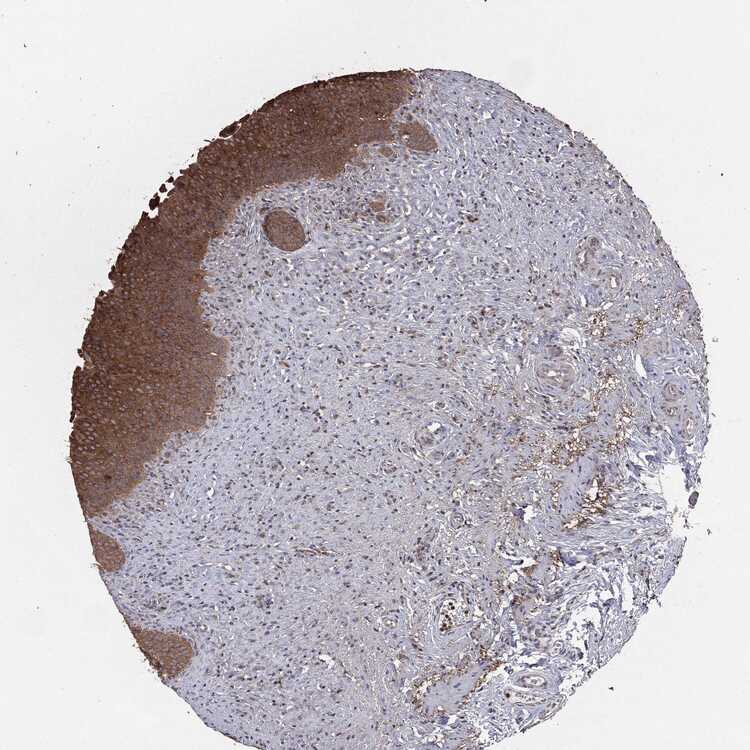

URINARY BLADDER - Antibody stainingi

Antibody staining in the annotated cell types in the current human tissue is reported as not detected, low, medium, or high, based on conventional immunohistochemistry profiling in selected tissues. This score is based on the combination of the staining intensity and fraction of stained cells. Each image is clickable and will lead to virtual microscopy that enables deeper exploration of all samples and also displays staining intensity scores, fraction scores and subcellular localization as well as patient and tissue information for each sample.

Antibody CAB080607Antibody CAB080608

Urothelial cells HighMedium